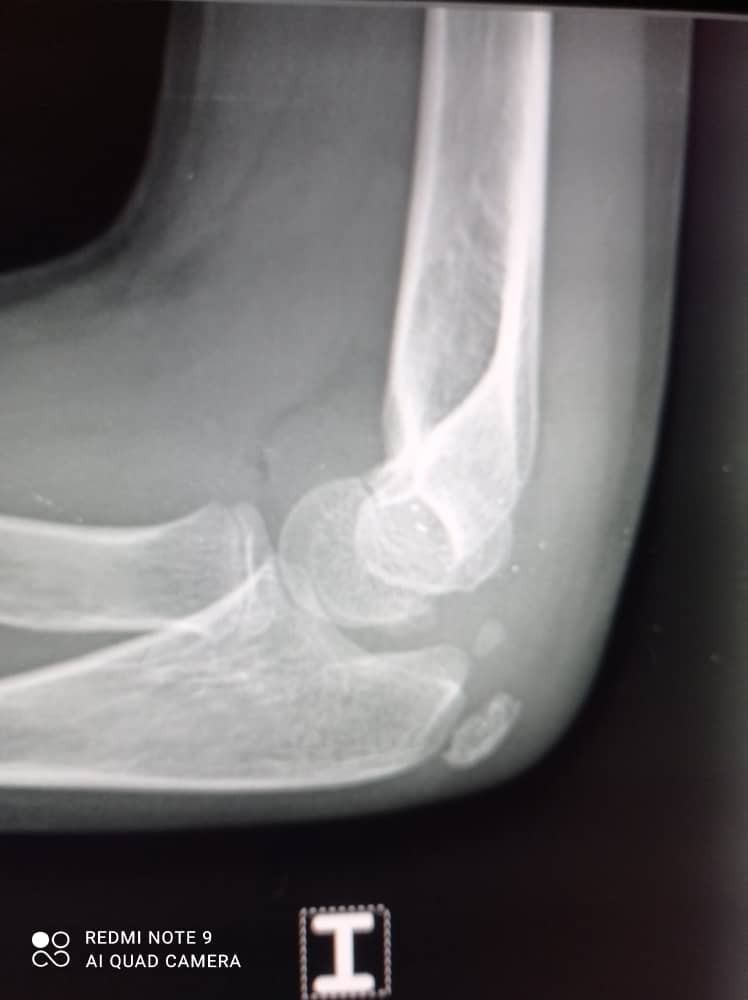

A few days ago, Samuel suffered a broken arm. While he now has a cast, he needs an ambulatory procedure and physical therapy to ensure a full recovery. Unfortunately, Samuel does not have insurance, and the costs of surgery and PT are more than his family can manage on their own. Your support will help cover these essential medical expenses and give Samuel the best chance to heal and return to his joyful, active life.